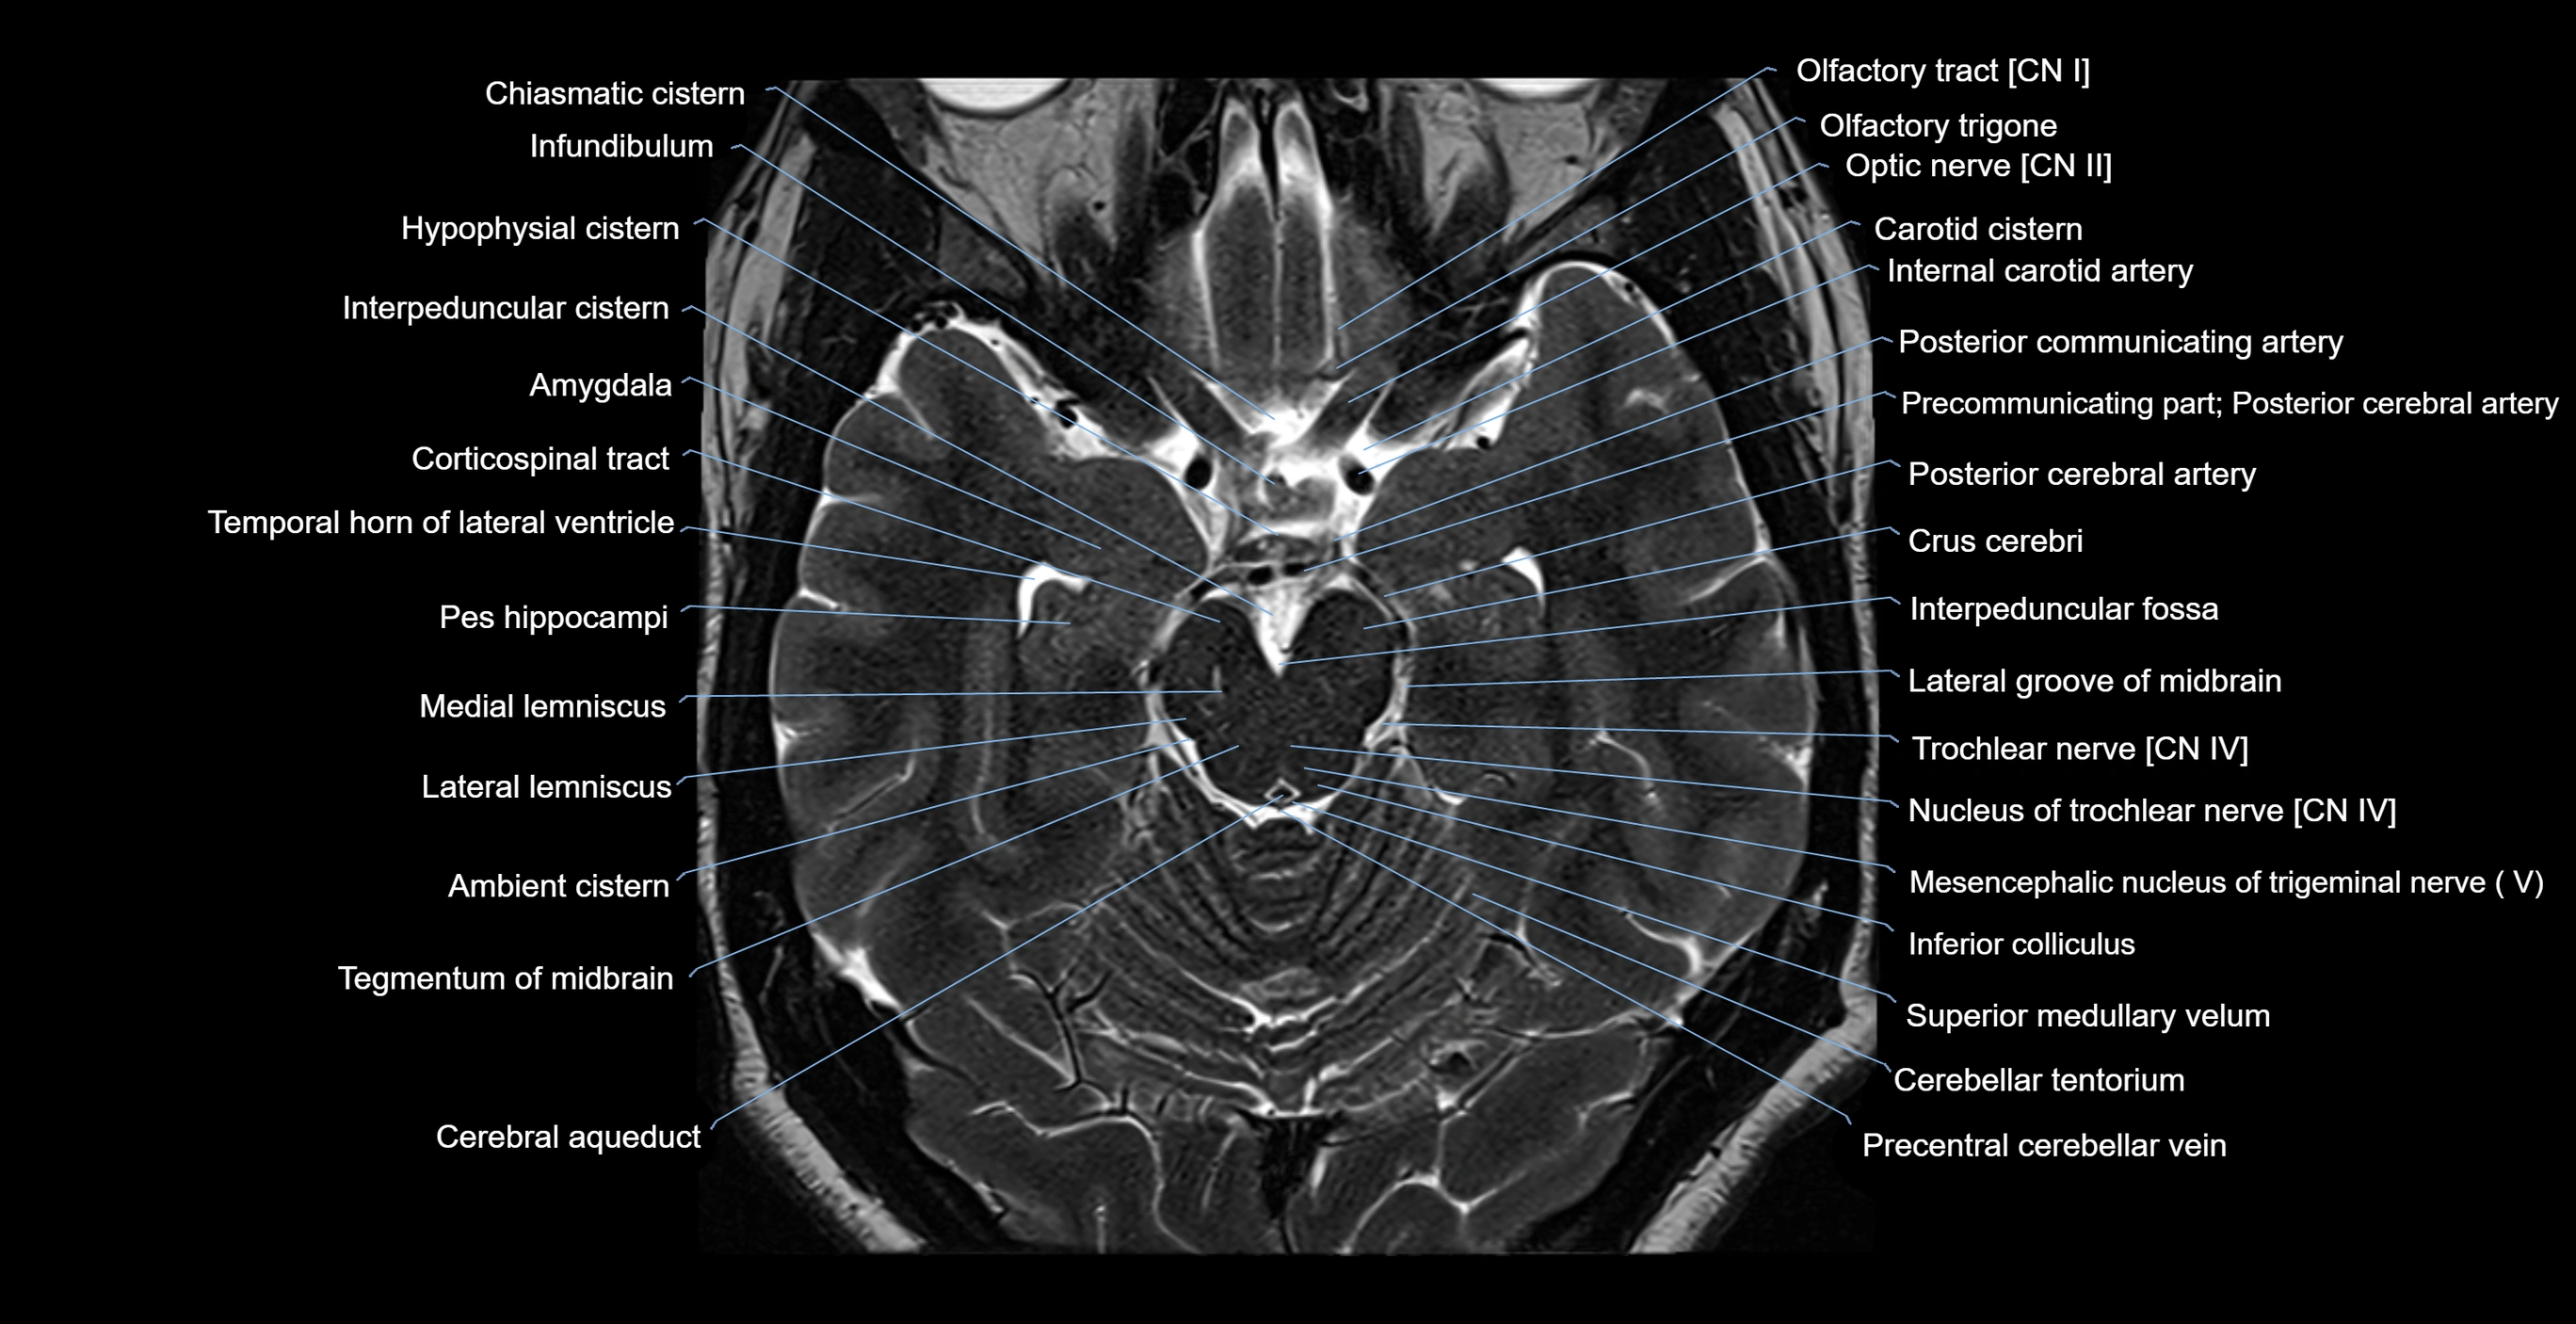

MRI images